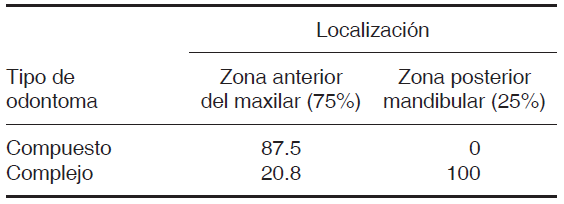

De los 12 casos, cuatro (33%) se presentaron en mujeres y ocho (67%) en hombres. La edad del diagnóstico de los odontomas fue en la segunda (58.33%) y tercera (41.67%) década de la vida (Cuadro I). El estudio anatomopatológico-clínico confirmó la presencia de ocho odontomas complejos (66.66%) y cuatro compuestos (33.33%). El 75% de odontomas se localizó en la zona anterior del maxilar superior (87.5% el diagnóstico fue odontoma compuesto y el 20.8% odontoma complejo), y el 25% en zona posterior del maxilar inferior todos con diagnóstico de odontoma complejo (Cuadro II).